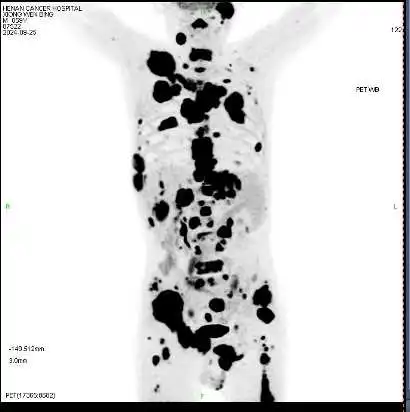

59岁闫先生近一年来经常全身疼痛。当地医院的检查结果显示,他的癌细胞已经转移至身体的多个部位——淋巴、骨骼、肝脏,四处“烽烟”让人不禁想问,这一切的起因在哪里?

(黑色区域为活跃的癌细胞)